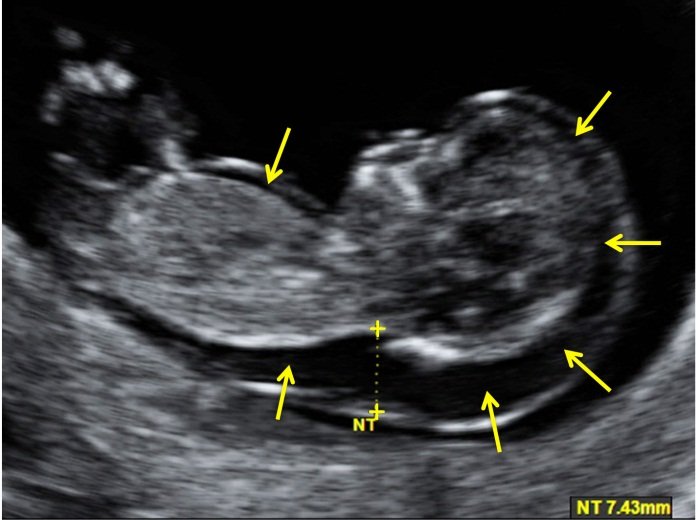

We provide quick and accurate Emergency Sonography, X-Ray, and Doppler services for immediate diagnosis.